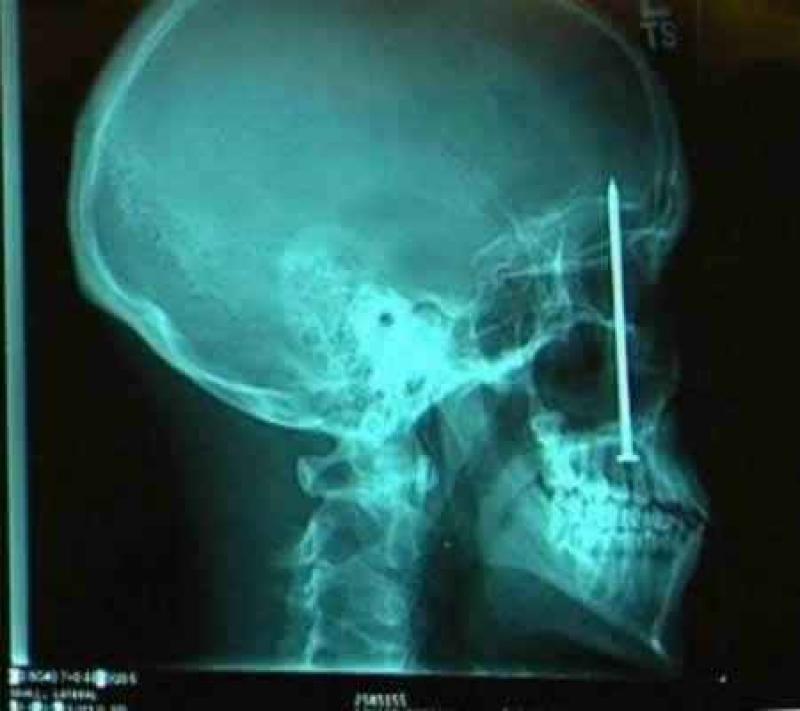

Röntgenfoto's zijn een medische uitvinding die ons al decennia lang helpt. Ze geven een nieuw gezichtspunt als het gaat om het vinden en behandelen van inwendige verwondingen. De machines kunnen opmerkelijke beelden vastleggen van het menselijk lichaam en ze documenteren vaak gruwelijke verwondingen. Een wonde van iemand zien, is al erg, maar als je ook kan zien wat de schade in het lichaam is, dat is nog veel erger. We hebben 12 tegelijk fascinerende, gruwelijke en hilarische röntgenfoto's op een rijtje gezet. Stel jezelf maar eens de vraag hoe iemand ooit aan die verwondingen is gekomen. We beginnen nog rustig.